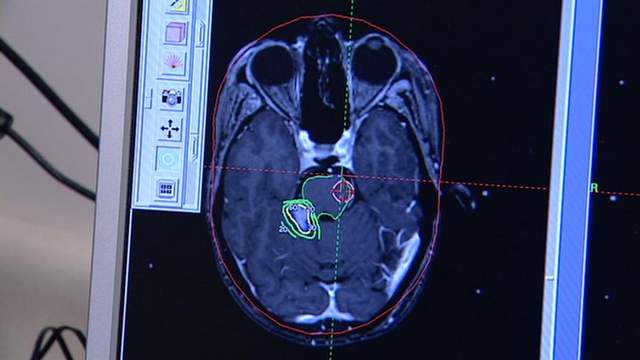

Looking at a picture of a patient's brain, doctors show how they can now remove an inoperable tumor, circled in green and yellow, which is dangerously close to the person's brain stem.

"We can tailor the dose of radiation to wrap around the tumor and yet deliver minimal or no dose to those critical structures that are within a millimeter or two of the tumor we are treating."